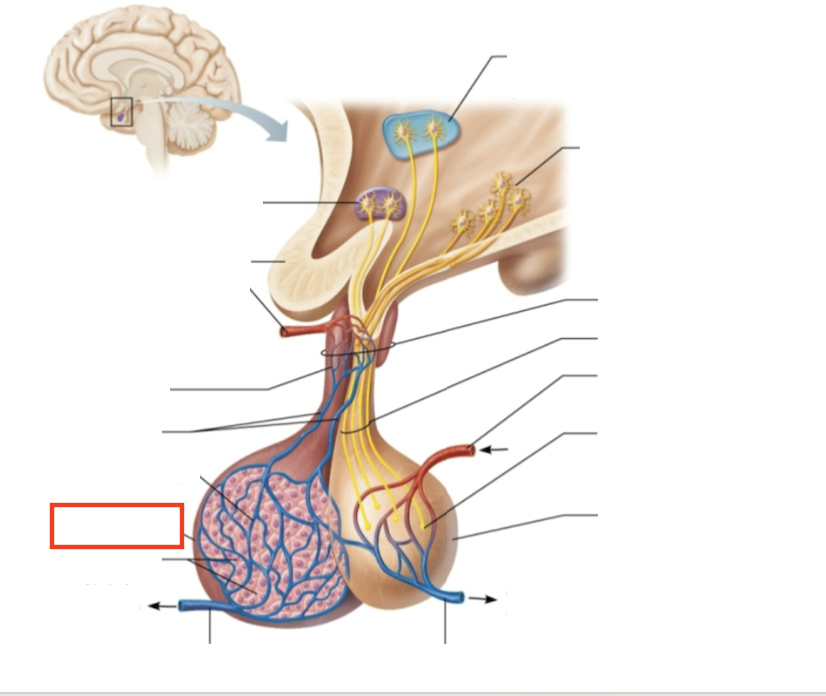

What structure is highlighted?

testes (male)

What are the target organs and effects of testosterone?

most cells of the body; promotes the maturation of the male reproductive organs, the development of secondary sex characteristics, sperm production, and sex drive

What hormone is produced by the testes?

testosterone

What stimulates testosterone production?

LH and FSH